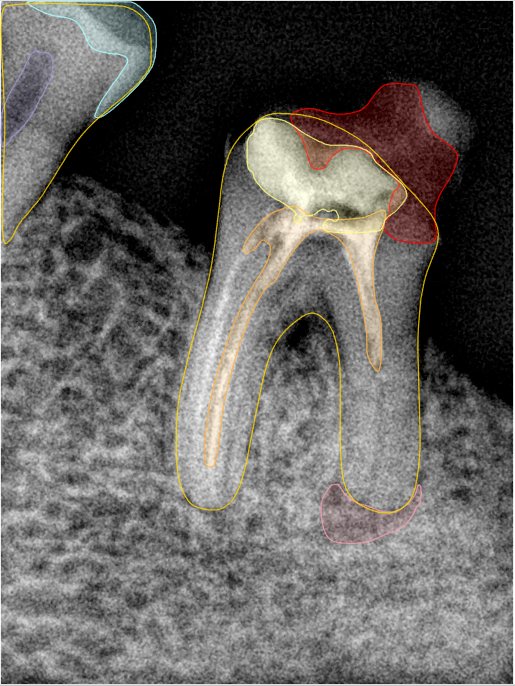

CR/DR 牙齿分割阶段记录

当前进展

- 完成了 CR/DR 牙齿相关分割训练

- 当前结果已经达到阶段预期,但仍有细节问题需要继续处理

相关测试

遇到的问题

- 训练过程中出现过 mask 下移问题

- 部分结果会出现 box 填充异常

- mask 边缘仍然有比较明显的锯齿感

参考

第二版算法问题测试

| 第一版 | 第二版 | 是否解决 | |

|---|---|---|---|

![]() | ![]() ![]() 边角识别有问题 龋齿识别不全 牙髓识别不全 | ![]() | 解决 |

![]() | ![]() 边角识别有问题 识别信息有误 自查(牙冠识别不全) | ![]() | 解决 |

![]() | ![]() ![]() 边角识别有误 大范围填充识别遗漏 | ![]() | 解决 |

![]() | ![]() 识别信息不全 | ![]() | 解决 |

![]() | ![]() ![]() 边角问题 牙胶识别不全 牙冠识别不全 | ![]() | 解决 |

![]() 换图片 | ![]() | ![]() 牙冠部分稍微白了一些就识别成小范围修补,部分判断异常 | 部分解决,修复类略敏感,牙冠部分稍微白了一些就识别成小范围修补,部分判断异常。 |

![]() | ![]() ![]() 牙冠识别不全 牙髓不全 根尖炎龋齿识别有误 | ![]() | 解决 |

![]() | ![]() | ![]() | 解决 |

![]() 换图片 | ![]() | ![]() | 解决 |

![]() | ![]() 牙冠识别有误 | ![]() | 解决 |

![]() 换图片 | ![]() ![]() 边角识别有误 | ![]() 修复类敏感 | 部分解决,图像过白,导致修复类判断异常。 |

![]() 换图片 | ![]() 牙冠识别不全 | ![]() 修复类敏感 | 部分解决,图像过白,导致修复类判断异常 |

结论:修复类出现了不鲁棒的情况,后续需要加入轮廓的扩充数据进行增强。